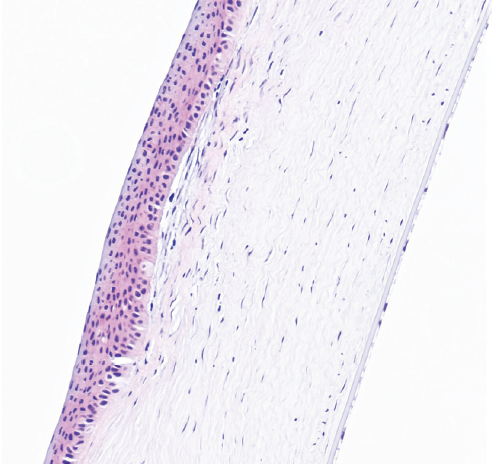

Режим 6. При данной мощности в месте воздействия роговица имеет нехарактерный вид. Эпителий полностью покрывает место вмешательства, однако базальные клетки эпителия кубические, сам эпителий истончён, неплотно прикреплён к строме. Строма в области повреждения практически на 1/4–1/3 толщины образована неплотно лежащими коллагеновыми волокнами с большим числом фиброцитов и единичными лимфоцитами. Десцеметова мембрана и энодотелий без изменений (рис. 4).

Рис. 4. Фрагмент роговицы через 3 мес. после воздействия в подгруппе 1а. Фульгурация, режим 6. Окраска гематоксилином и эозином. Увеличение ×40

Fig. 4. Fragment of the cornea 3 months after exposure in subgroup 1a. Fulguration, mode 6. Stained with hematoxylin and eosin. Magnification ×40

На первом этапе эксперимента воздействие на роговицу в режиме 5 как клинически, так и гистологически выглядело недостаточным. Изменения охватывали лишь 10–15 % передней стромы. Учитывая, что в норме толщина роговицы кролика в центре составляет примерно 350 мкм, воздействию подвергались лишь около 50 мкм стромы. При воздействии в режиме 6 и 7 через 3 мес. изменения стромальной структуры распространялись примерно на 150 мкм. Воздействие в режиме 8, по нашему мнению, является избыточным. У кролика на этом режиме воздействия были самые грубые изменения в строме. Кроме того, в патологический процесс вовлекалась десцеметова мембрана.